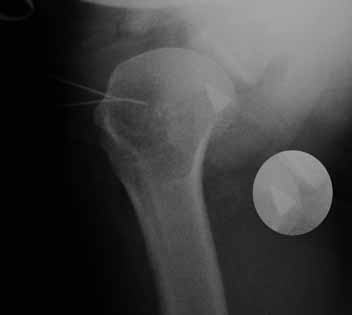

Больная В. 41 год. Во время выполнения операции Розенштейна – пересечение сухожилия двуглавой мышцы плеча

(транспозиции сухожилия двуглавой мышцы плеча, с проведением ёё под ротаторами плеча, к клювовидному отростку) произошел перелом конца съёмного лезвия скальпеля (Фирма: TRO-Microcut. №21; Lot 21/889-01 Exp: 2013-02).

Снимок сделан во время операции в положении бльного на спине - аксиальная проекция. Игольчате метки - передняя поверхность плечевого сустава в этом мете осуществлен доступ. Прямая проекция обрезана. Фрагмент рапологается по центру головки на самом краю снимка.

Предполагаю, после востановления мягких тканей 2-4 недели) выполнить артроскопическое вмешательство (будет использован поврежденный артроскоп 6 мм).